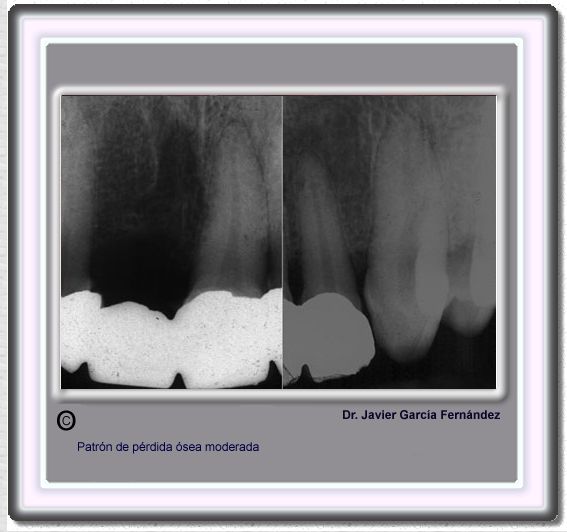

image 183